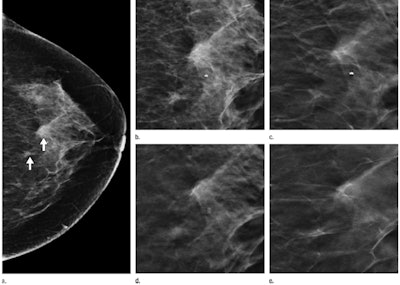

Images of a 53-year-old woman who underwent screening mammography. (a) Craniocaudal 2D view shows two asymmetries (arrows) at middle to posterior depth, central in the breast. (b) Craniocaudal 2D view of the two asymmetries. Single tomosynthesis section images of the left breast in craniocaudal view in the (c) lower breast, (d) midbreast, and (e) upper breast demonstrate that the asymmetries are caused by superimposed tissue. No recall was necessary. Images courtesy of RSNA.